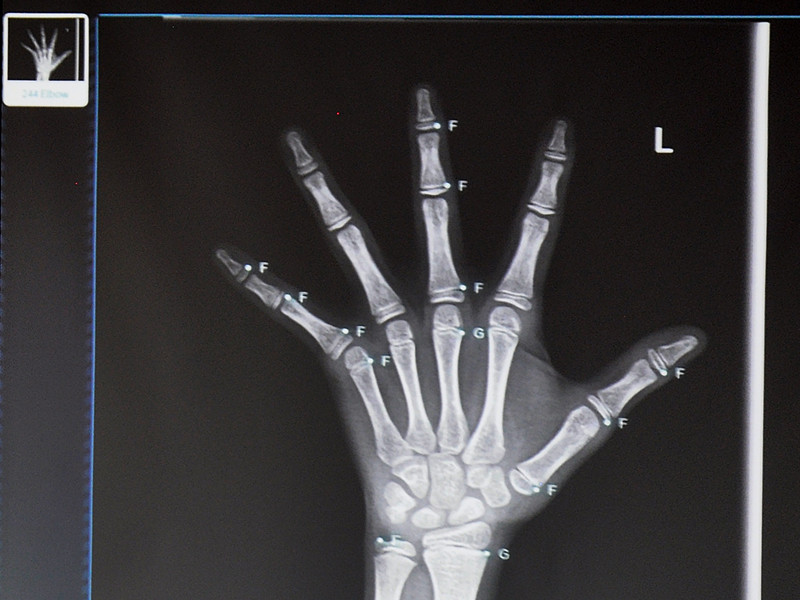

浙江省儿保主任医师、内分泌科科室副主任董关萍表示,影像信息主要选择正常儿童的骨龄影像信息,这是由于骨龄检测的特殊性所致。骨龄提前常见的三种表现形式包括矮小、早熟、肥胖,因此只有与正常的骨龄影像进行比对,才能真正判断患者的骨龄是否正常。与此同时,董关萍还表示,与依图医疗合作,医院和医生个人都希望可以通过不断校验骨龄人工智能产品,从而打造属于中国的骨龄图谱,真正做到造福人类。

据了解,依图医疗与浙江省儿保共同打造的国内首个骨龄人工智能产品目前已经嵌入医生实际工作流。那么,人工智能切入临床的难点又是什么呢?依图医疗副总裁郑永升表示:

目前,依图医疗与浙江省儿保共同研发的骨龄人工智能产品还处于不断校验、不断完善的阶段,从“单中心”到“多中心”的发展之路还在继续。与此同时,依图医疗的AICARE®胸部CT智能辅助诊断、AICARE®儿童骨龄智能辅助诊断、AICARE®小儿常见病智能辅助诊断、AICARE®病历智能搜索引擎、AICARE®临床智能科研平台等一系列产品也在同步走向市场。